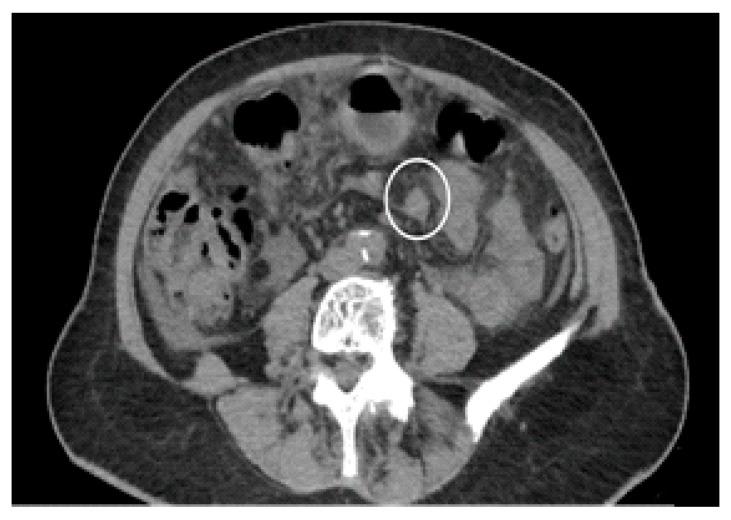

Peritoneal carcinosis is a condition characterized by the spread of cancer cells to the peritoneum, which is the thin membrane that lines the abdominal cavity. It is a serious condition that can result from many different types of cancer, including ovarian, colon, stomach, pancreatic, and appendix cancer. The diagnosis and quantification of lesions in peritoneal carcinosis are critical in the management of patients with the condition, and imaging plays a central role in this process. Radiologists play a vital role in the multidisciplinary management of patients with peritoneal carcinosis. They need to have a thorough understanding of the pathophysiology of the condition, the underlying neoplasms, and the typical imaging findings. In addition, they need to be aware of the differential diagnoses and the advantages and disadvantages of the various imaging methods available. Imaging plays a central role in the diagnosis and quantification of lesions, and radiologists play a critical role in this process. Ultrasound, computed tomography, magnetic resonance, and PET/CT scans are used to diagnose peritoneal carcinosis. Each imaging procedure has advantages and disadvantages, and particular imaging techniques are recommended based on patient conditions. Our aim is to provide knowledge to radiologists regarding appropriate techniques, imaging findings, differential diagnoses, and treatment options. With the advent of AI in oncology, the future of precision medicine appears promising, and the interconnection between structured reporting and AI is likely to improve diagnostic accuracy and treatment outcomes for patients with peritoneal carcinosis.

腹膜癌是一种以癌细胞扩散至腹膜为特征的病症,腹膜是衬于腹腔的一层薄膜。它是一种严重的病症,可由多种不同类型的癌症引发,包括卵巢癌、结肠癌、胃癌、胰腺癌和阑尾癌。腹膜癌中病变的诊断和定量对于该病症患者的管理至关重要,而影像学在这一过程中发挥着核心作用。放射科医生在腹膜癌患者的多学科管理中起着至关重要的作用。他们需要对该病症的病理生理学、潜在肿瘤以及典型的影像学表现有透彻的了解。此外,他们需要知晓鉴别诊断以及各种可用影像学方法的优缺点。影像学在病变的诊断和定量中起着核心作用,放射科医生在这一过程中起着关键作用。超声、计算机断层扫描、磁共振成像和正电子发射断层显像/计算机断层扫描(PET/CT)用于诊断腹膜癌。每种成像检查都有其优缺点,会根据患者情况推荐特定的成像技术。我们的目的是向放射科医生提供有关合适技术、影像学表现、鉴别诊断和治疗方案的知识。随着人工智能在肿瘤学中的出现,精准医学的未来似乎很有前景,结构化报告与人工智能之间的相互联系可能会提高腹膜癌患者的诊断准确性和治疗效果。